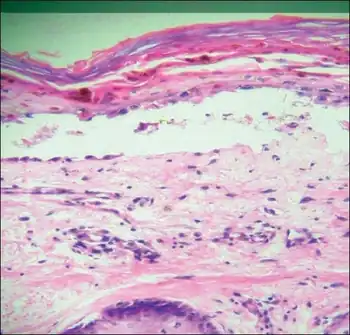

| Transfusion associated graft versus host disease -Mononuclear cell infiltration and inflammation of affected epithelium, with focal vacuolation of basal epithelial cells | |

TA-GvHD can be suspected from a biopsy of the affected skin or liver,[3] and established by HLA analysis of the circulating lymphocytes. This testing can identify circulating lymphocytes with a different HLA type than the tissue cells of the host.